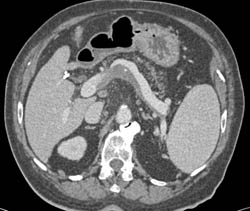

Partial Thrombosis of the Portal Vein